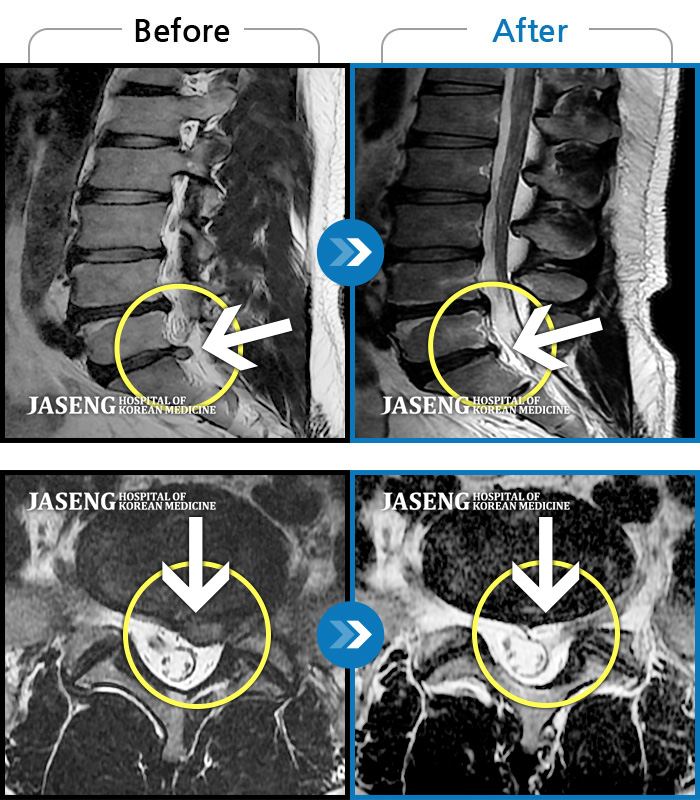

저는 교통사고 후유증과 운동부족,잘못된 자세등으로 간혹 허리가 아팠습니다.. 근데 최근 몇일간 무리한후에 허리가 아프고 왼쪽 하지방사통과 저린감이 너무 심하여 밤에 잠도 제대로 들기 어려울 정도 였습니다...MRI를 찍으니 디스크라고 하더라구요..ㅠ..ㅠ 예상은 하고 있었지만 20대후반에 디스크라니...좌절감과

우울감이 심하였습니다.. 무조건 수술은 안하리라는 생각에 원장님을 찾아뵈었습니다..저한테는 어떻게보면 행운이였나봅니다...

앞으로 치료계획에 대해 상세히 설명해주시며 믿음과 희망을 주셨습니다 ..마음이 한결 가벼워 졌습니다..

추나, 침, 약침, 물리치료, 약물(한약)요법을 병행하며 현재 2주가 조금 지났는데...저도 놀랄정도로 왼쪽 하지방사통은 거의 없어졌어요..감동감동 ㅠ..ㅠ

치료에 대해 믿음이 있었지만 이렇게 빨리 회복이 될지는 저도 놀랐습니다...